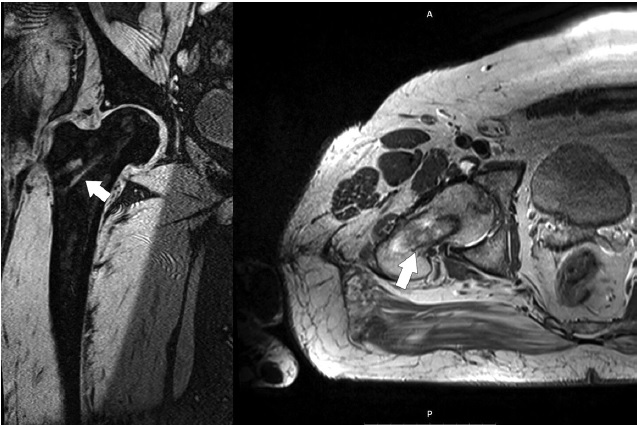

MRI evaluation 6 months after surgical intervention showed a similar picture in patients of both groups, which was obviously connected with the homogeneity of developing processes of bone autograft remodeling in the intervention area. However, when analyzing the MRI of the hip joint 12 months after operation, we observed a marked increase in the spreading zone of bone marrow oedema of the femoral head, as well as the presence of persisting and pronounced perifocal oedema of the transplant area in 5 patients of the control group (Fig. 12).

Fig. 12. MRI of the right hip joint 12 months after the core decompression using the light bulb technique: a pronounced trabecular oedema is observed in the area of grafting, spreading to the metaphyseal region (indicated by arrow)